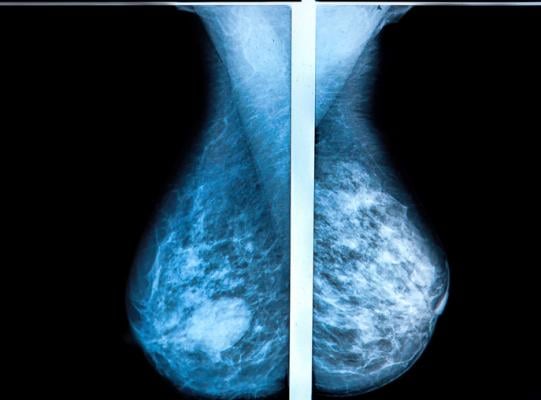

So it was with the introduction of three-dimensional tomosynthesis mammography, which allows radiologists and oncologists to see deeper into breast tissues by taking multiple images and allowing specialists to interpret each layer almost as if they were reading a book.

The technology promised greater efficiency at cancer detection and fewer callbacks on patients for whom the interpretation of results was unclear or uncertain.